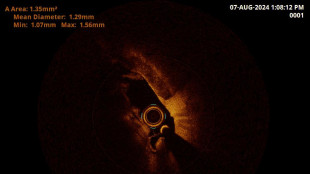

Chirurgia con 3D, neonato salvato dalla cecità

Su un bambino di 40 giorni alle Molinette, primo caso al mondo